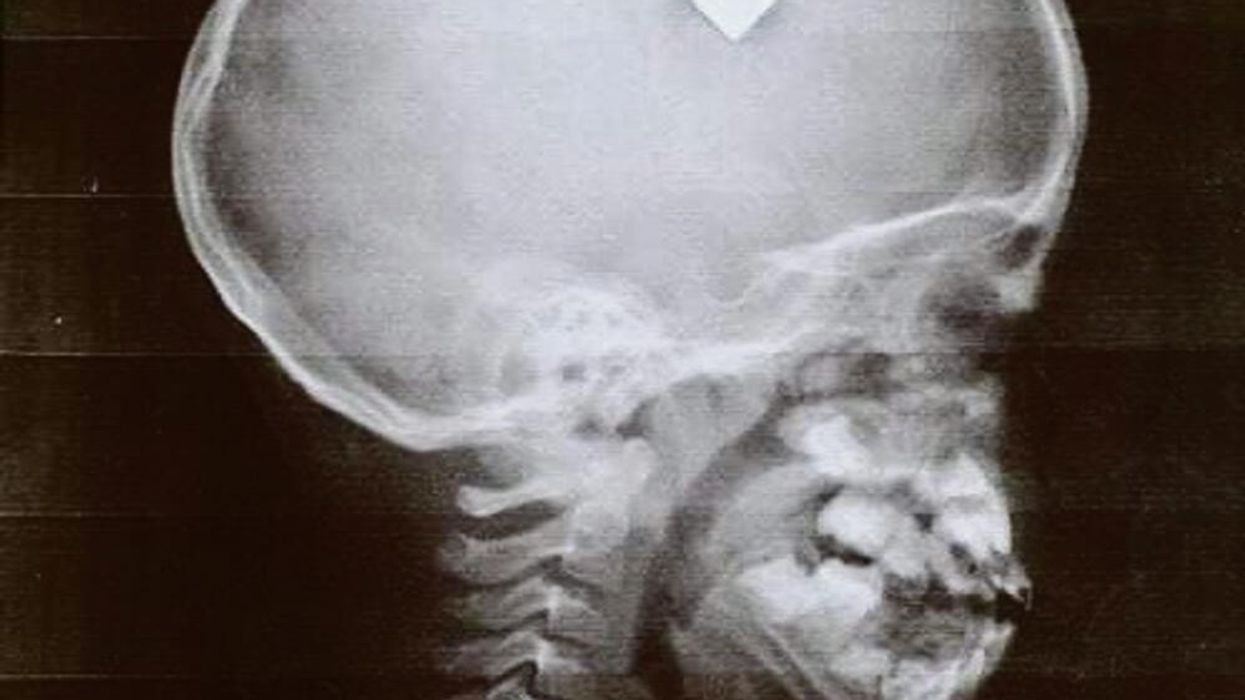

Për të mos humbur më shumë kohë, e dërgoi me urgjencë në spital ku vogëlushi i është nënshtruar kontrolleve të detajuara. Në rëntgen u konstatua qartë se kishte një plumb në kokë.

Mjekët mbetën të shokuar sikurse edhe prindërit e tij. E duke pasur parasysh që intervenimi kirurgjik nuk mund të kryhej menjëherë, atë e kishin vënë në komë, derisa prindërit mblodhën paratë e kërkuara për operacionin e komplikuar – nxjerrjes së plumbi nga koka e Adrianit.

Operacioni është kryer më 6 gusht dhe ka përfunduar me sukses, kurse vogëlushit do t’i duhet të qëndrojë në spital edhe për disa javë. Mjekët duan të binden që plaga nuk ia ka dëmtuar trurin dhe të mos ketë ndonjë pasojë.